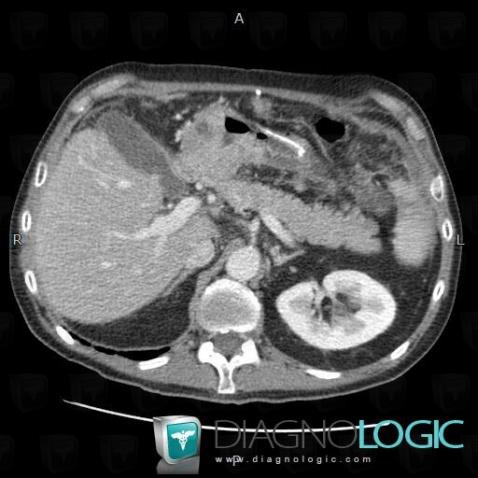

Gastric carcinoma, Stomach, CT

Here is the specific information in the key image above:

- Diagnosis Gastric carcinoma, Location(s) Stomach, with gamuts Gastric mass or filling defect